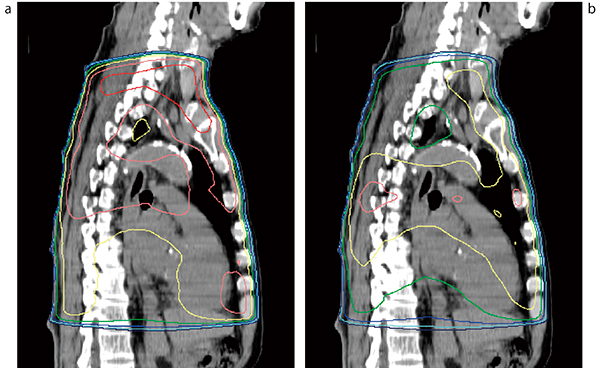

腰椎から骨盤に及ぶ多発性骨転移の痛みには,6〜8Gyの半身照射を行っている(図1)。悪心や嘔吐は放射線治療1時間前のグラニセトロン内服でほとんど予防できる。痛みが再燃した場合や効果が不十分な場合は,再度半身照射を行うことも可能である。

図1 腰椎〜骨盤に対する半身照射

target volumeは設定せず,数値入力でマルチリーフコリメータ(MLC)を設定し両腎と消化器を遮蔽している。